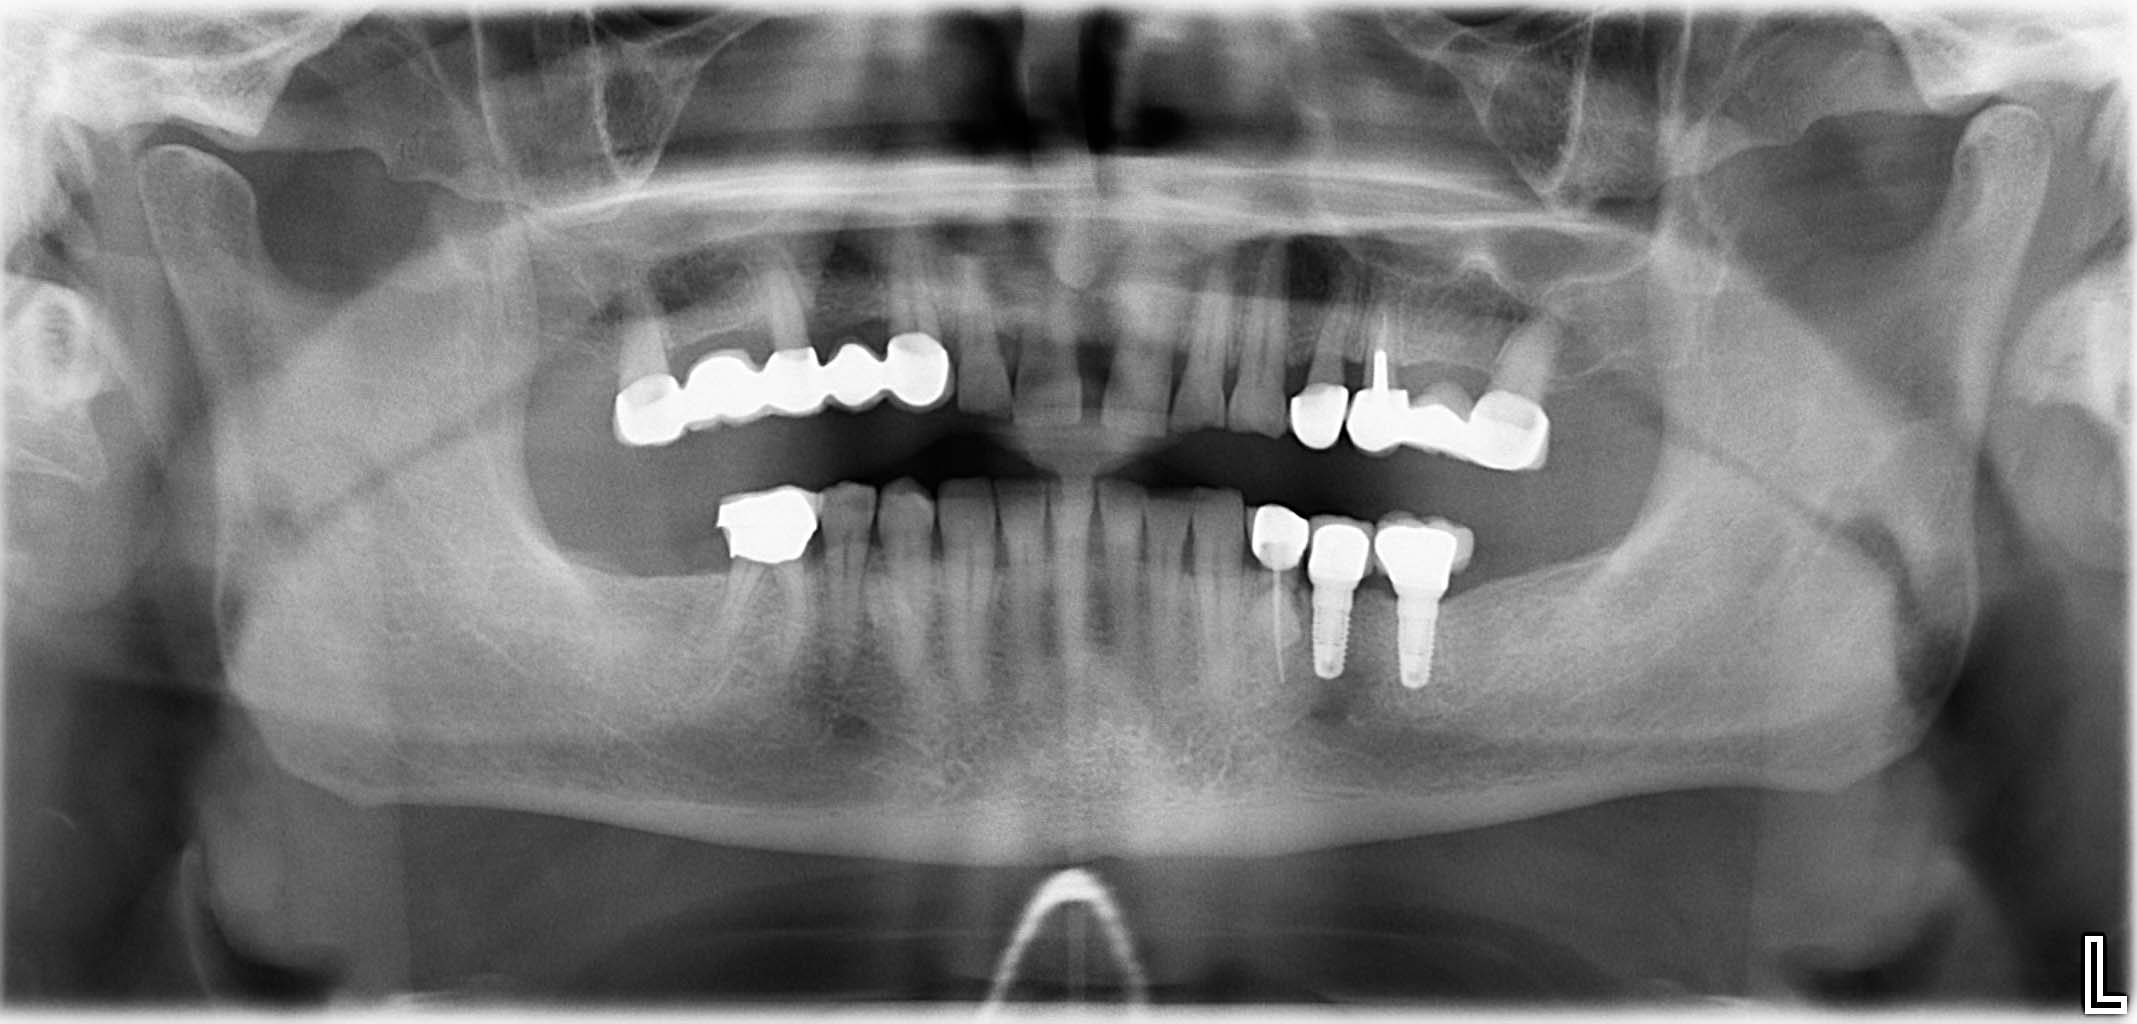

Erfolgreich implantierte Patientenfälle (klinische Fotos)